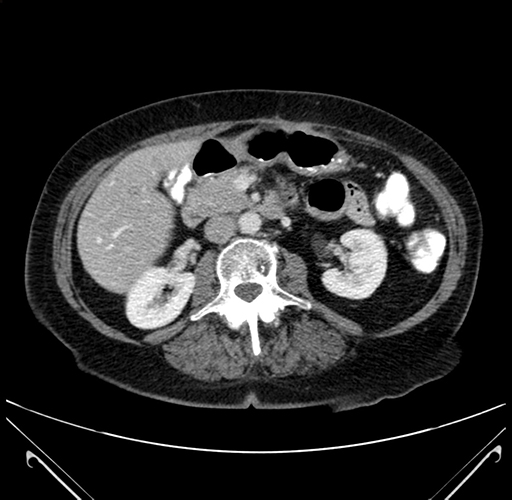

Pre-Chemo: Axial Venous

Axial Venous